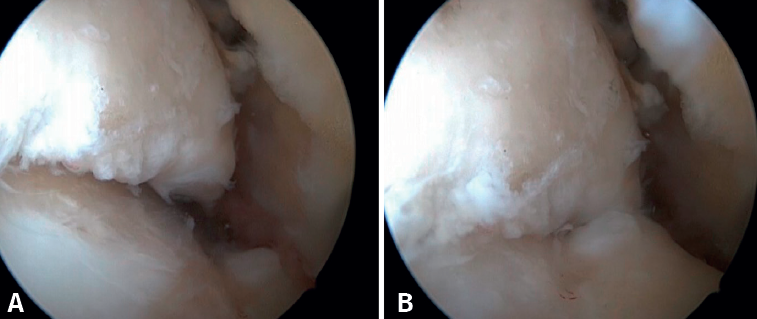

Anterior ankle impingement is defined as pain and/or limitation of range of motion that occurs with dorsiflexion of the ankle, due to the presence of soft tissue or bone interposed between the joint surfaces. A distinction is made between soft tissue impingement (synovial proliferation, thickening of Bassett's ligament, capsular adhesions), bony impingement (osteophytes or alterations in the ankle or hindfoot axis) (Figure 1) and mixed impingement (Table 1). AAI in turn can be subdivided into central, anterolateral and anteromedial impingement(8), with the first two being the most common presentations(9). Anterolateral AAI usually involves soft tissue, while anteromedial AAI is usually caused by a spatial conflict between osteophytes of the talar neck and anterior to the medial malleolus in dorsiflexion(9,10). AAI is the most common cause of anterior ankle pain that worsens with dorsiflexion. However, posterior impingement may be more frequent in certain patient groups, such as dancers or football players, due to repetitive movements in forced plantar flexion(4).

Bony AAI due to osteophytes has also been linked to the presence of chronic instability. It has been postulated that altered joint kinematics secondary to ligament insufficiency favors the development of osteophytes in the anterior region of the tibia and talus(36,37). Recent studies have questioned the theory of repeated capsular traction as the origin of osteophytes in sports(38), as it is easily demonstrated that osteophytes are located intra-articular within the capsular insertion, in the context of ankle arthroscopy (Figure 2). Therefore, ankle dorsiflexion arthroscopy is essential to safely resect osteophytes without damage to the capsule or overlying structures, whereas the classical traction technique (invasive or otherwise) would make resection extremely difficult, and is thus not recommended nowadays for routine use(3,39). Vega distinguished between two types of osteophytes(3), according to whether they are caused by repetitive trauma (peak-shaped) or instability (visor-shaped). The concept of micro-instability is associated with repetitive micro-trauma, which could be the origin of osteophytes with this characteristic morphology (Figure 3).